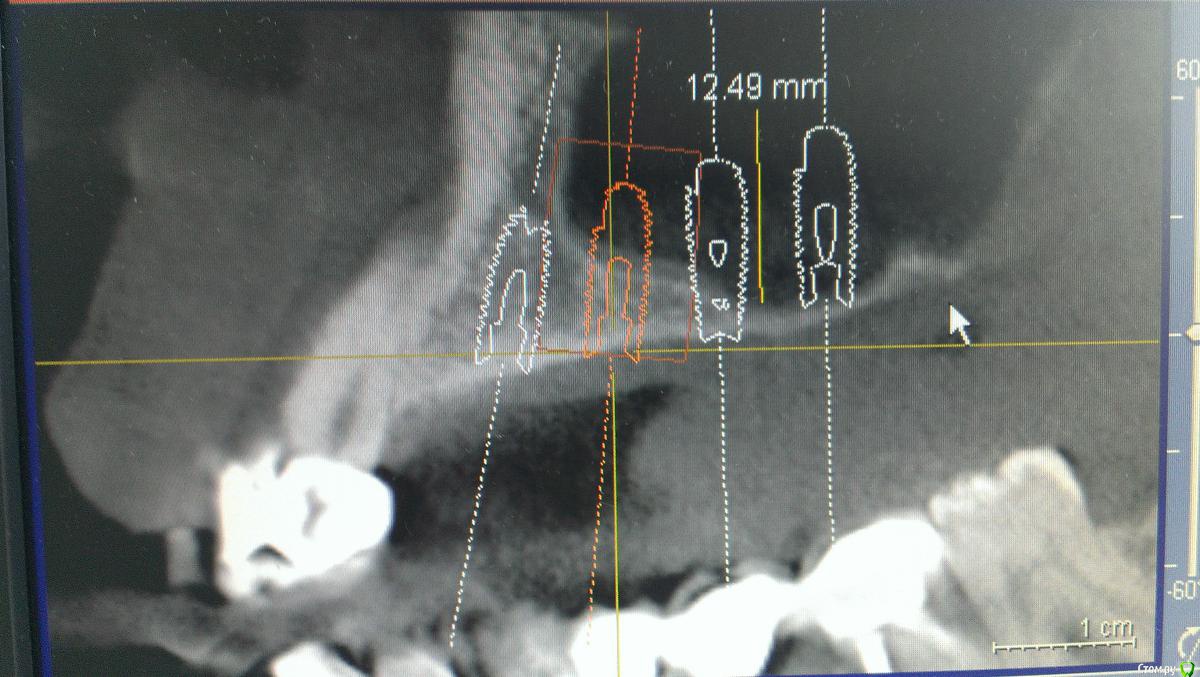

AlexFox Опубликовано 13 июля, 2016 Поделиться Опубликовано 13 июля, 2016 Доброго времени суток,коллеги.Огромная просьба к имплантологам поделиться своим мнением по-поводу клинического случая.Пациенту 45 лет,жалобы на отсутствие жевательной группы зубов во втором сегменте.Для постановки имплантов требуется синуслифтинг.Меня настораживает малый объем имеющейся костной ткани при большом объеме поднятия дна.Плюс слизистой на кт я вообще не вижу.Хотелось бы узнать ваше мнение об этом. Ссылка на комментарий

BugDan Опубликовано 14 июля, 2016 Поделиться Опубликовано 14 июля, 2016 (изменено) Я бы сделал синус с ауто-ксено 1:1 по причине чистой кортикалки в области моляров.Ставить ли импланты сразу или нет зависит от макродизайна имплантатов котрыми вы планируете пользоваться и опыта в первую очередь.На картинках планирования 23 стоит далековато от 22 , винт 5 стоит чуть медиальнее чем надо, а 6 сильно медиальнее чем нужно. Для страховки просмотрите латеральную стенку синуса на предмет артерии. Изменено 14 июля, 2016 пользователем BugDan Ссылка на комментарий

AlexFox Опубликовано 14 июля, 2016 Автор Поделиться Опубликовано 14 июля, 2016 Спасибо,коллеги.На основании ваших замечаний изменил постановку имплантов.Выложил фото,буду рад вашим коментариям Ссылка на комментарий